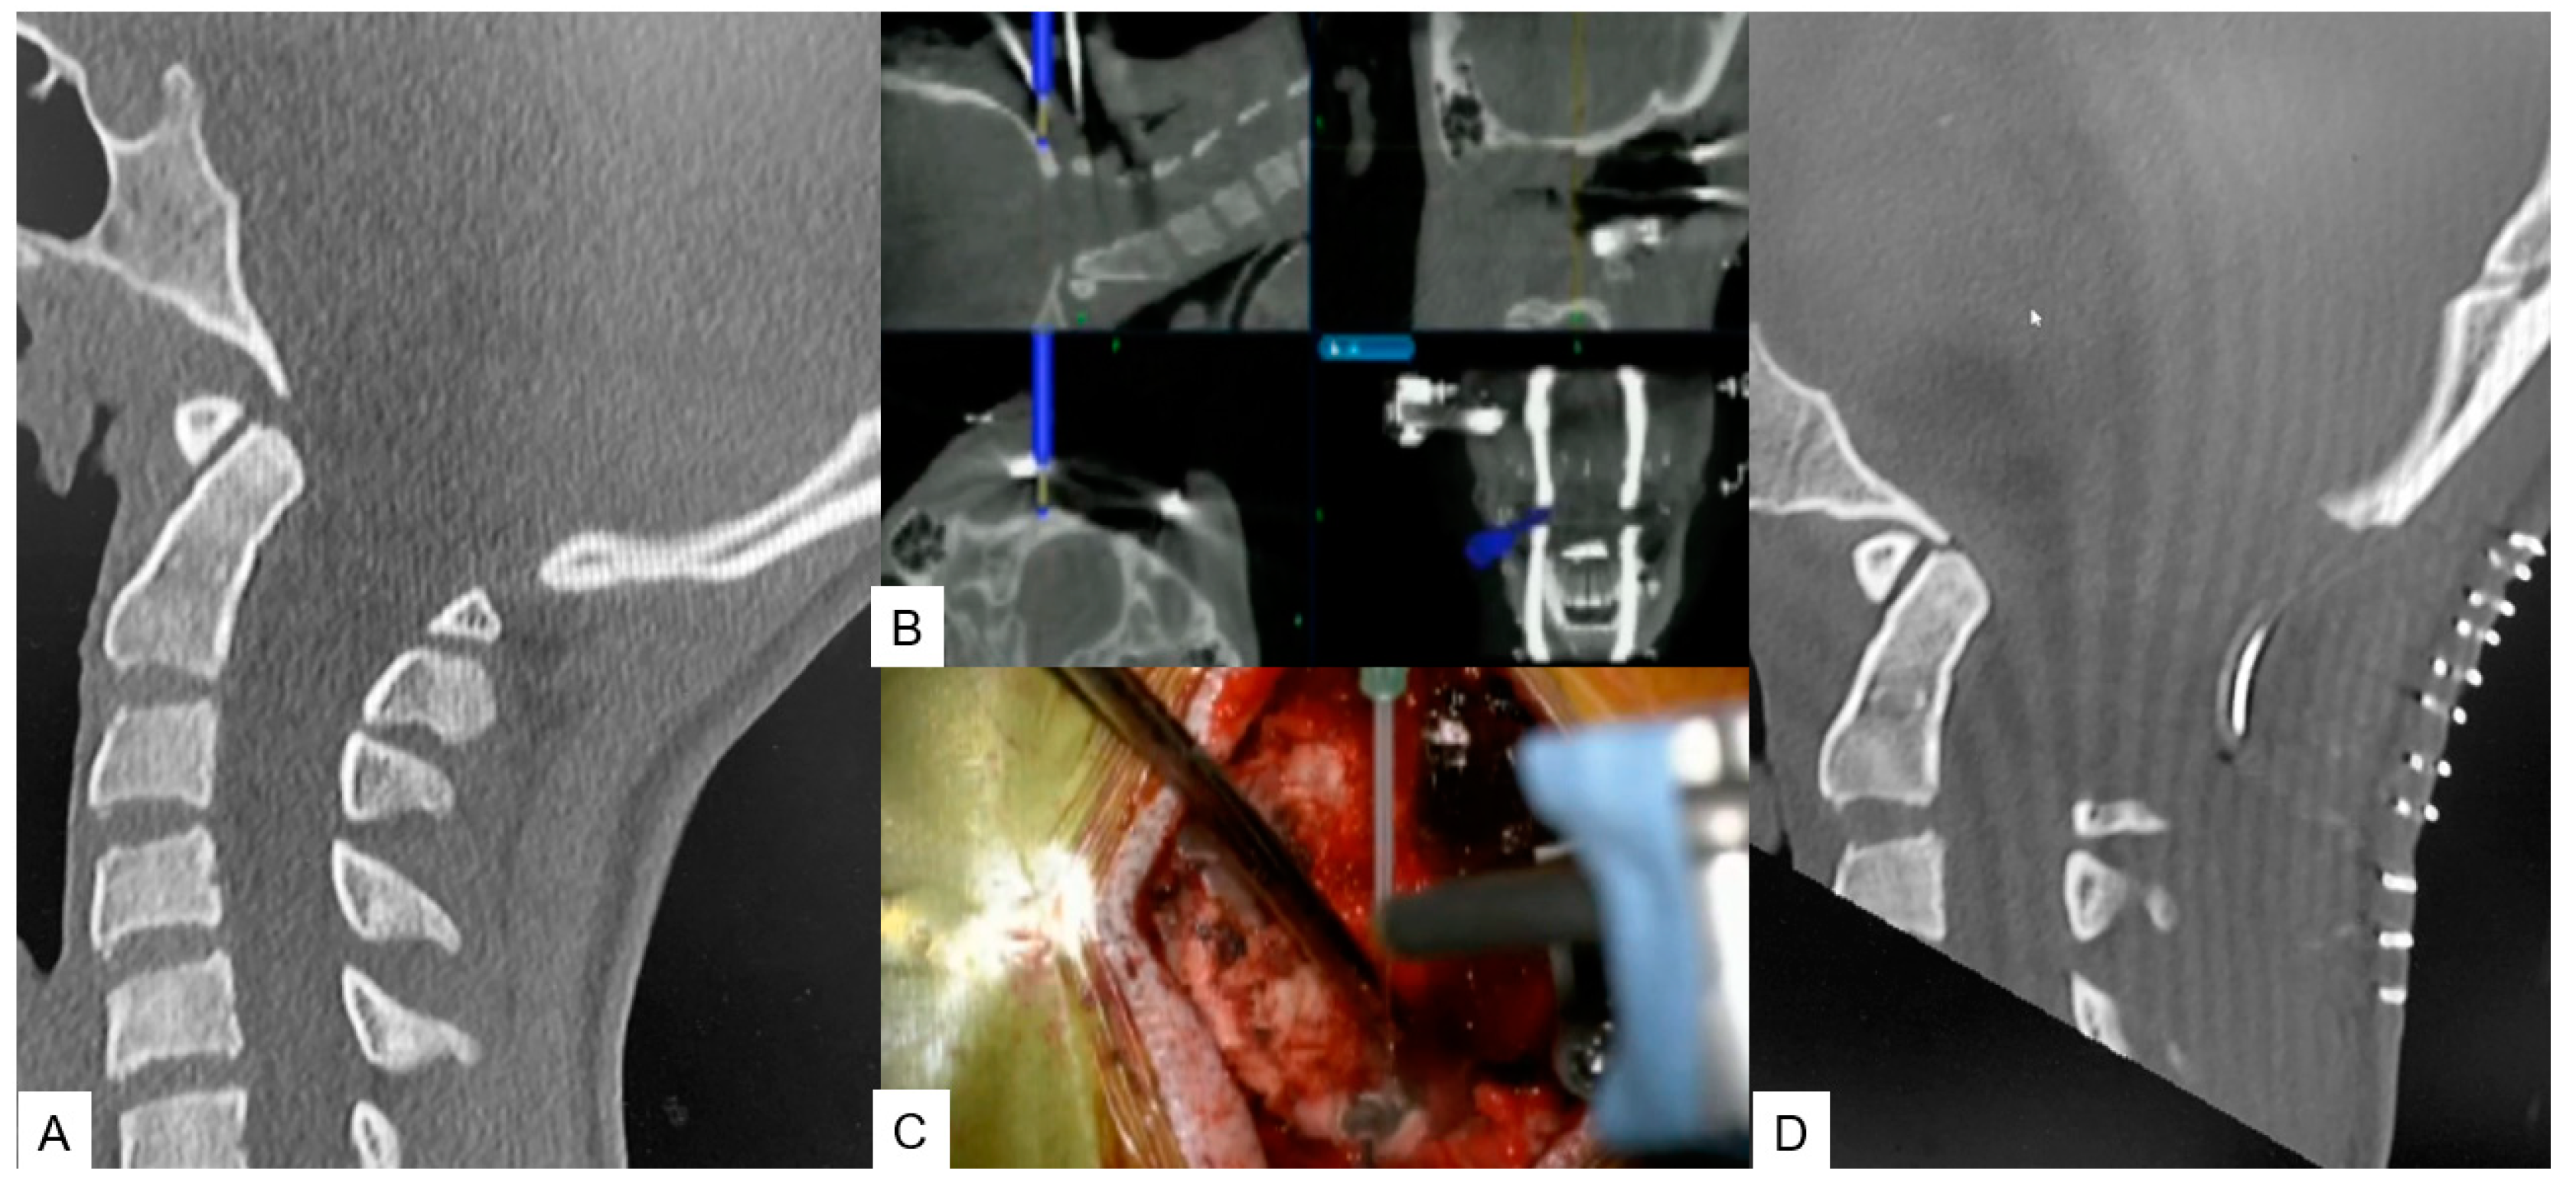

Figure 2. Case 2, 14 years old female, Chiari malformation, Foramen magnum decompression. A: Preoperative occipitocervical CT sagittal reconstruction, B: Intraoperative navigation image, C: Intraoperative image, F: Postoperative occipitocervical CT sagittal reconstruction.

2.2.1. Posterior Fossa Decompression for Chiari Malformation

The surgical technique starts with an approximate skin incision of 7 cm from the greater occipital protuberance down to C2 spinous process, followed by subperiosteal detachment of dorsal cervical muscles from linea alba, spinous process and C2 lamina to avoid excessive bleeding. The most convenient point used for reference frame attachment for O-arm scanning is C2 spinous process. Next, by use of a high-speed burr the C1 posterior arch is resected. In some cases, when severe tonsillar herniation exists, we advise for C2 lamina resection. Excellent knowledge of anatomy is needed to avoid vertebral artery injury. Preoperatively, anatomical variations should also be considered. Thirdly, navigation assisted craniotomy is performed. Usually, 3cm peripheric to foramen magnum is considered adequate. The merit of navigation is the ability to verify the exact bone width and location of the foramen ma witgnum to avoid intraoperative complications. During the last step, duroplasty following ultrasonic monitor verification is performed. In case of inadequate decompression, we recommend extension of bone resection or duroplasty by use of artificial dura.